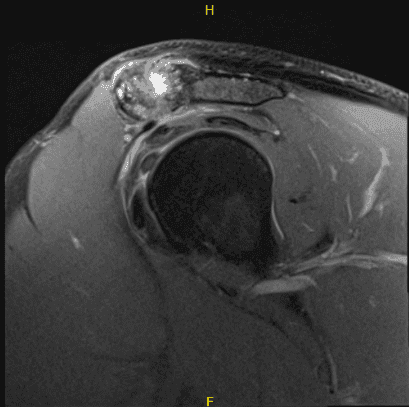

El paciente presentó un resultado de resonancia magnética que mostró una ruptura de la superficie articular de alto grado parcial en la inserción del tendón supraespinoso. Desgarro de la superficie articular de bajo grado y grosor parcial del tendón infraespinoso distal. Artrosis moderada de la articulación AC.

Un pequeño espolón subacromial predispone al paciente a un impacto externo. Desgarro no desplazado del labrum posterosuperior. Bursitis subdeltoides subacromial leve.

Imágenes de artroscopia intraoperatoria